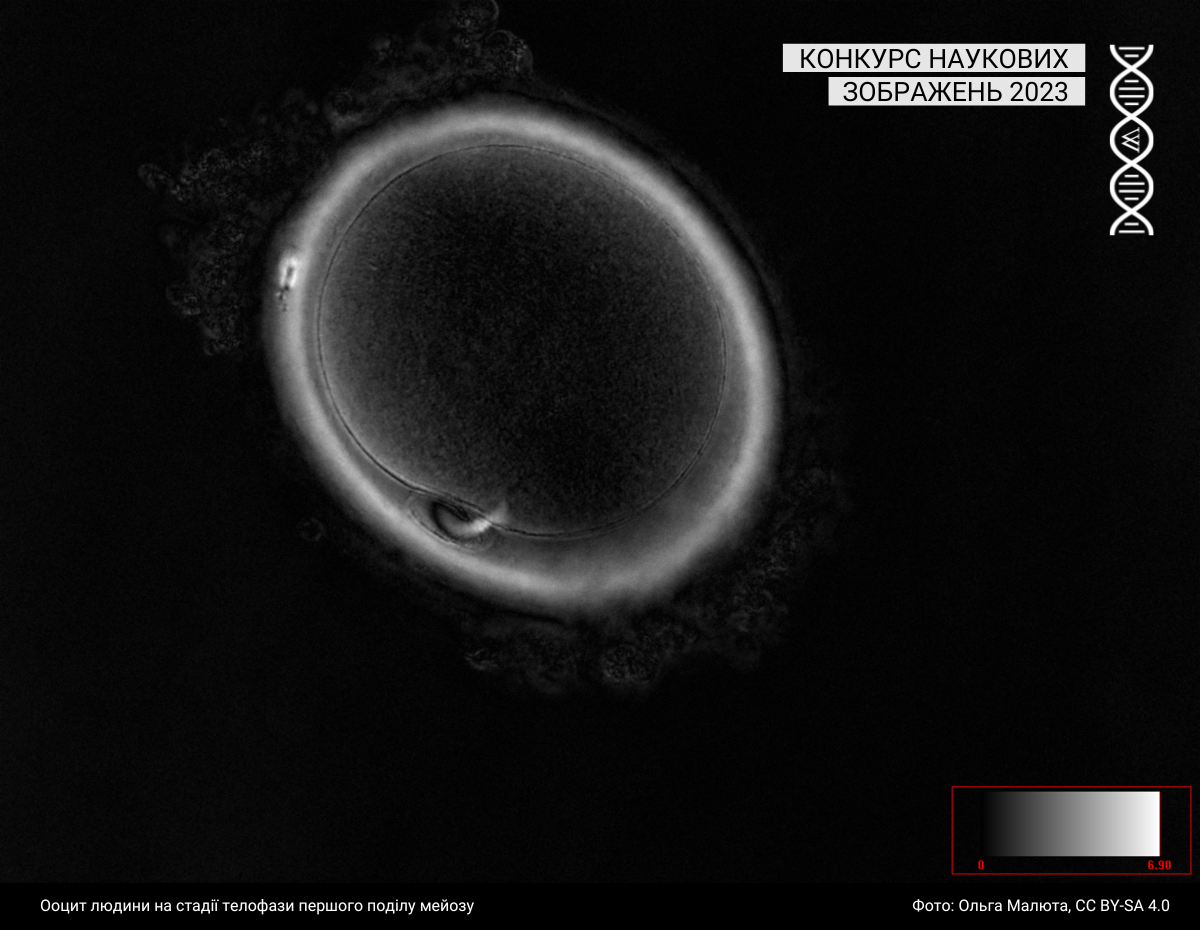

Під цю категорію підпадають світлини, зроблені за допомогою різних методик мікроскопії. Минулого року до цієї категорії учасники та учасниці завантажили 43 фотографії.

Спеціальна відзнака журі

Журі призначили спеціальну відзнаку серії зображень однієї авторки: https://w.wiki/99qJ, https://w.wiki/99qK, https://w.wiki/99qL, https://w.wiki/99qM